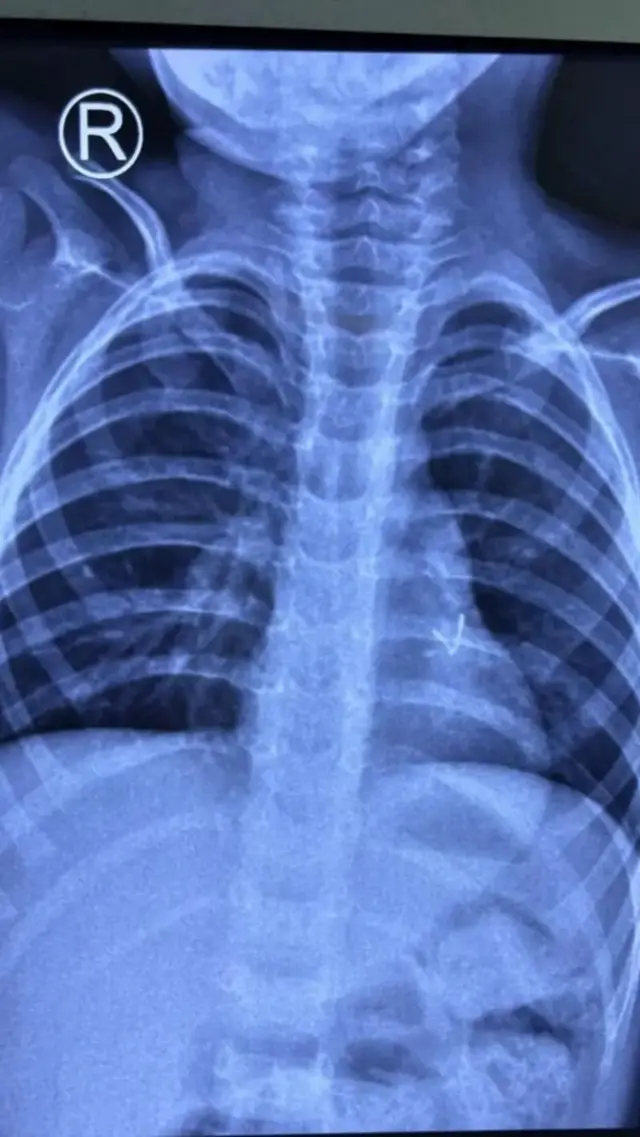

ஆனாலும், சிறுவனின் பிரச்னைகள் குறையாததால், மேலும் பரிசோதனைகள் செய்ய வேண்டியதாயிற்று. சிடி ஸ்கேன் செய்தபோது, இடது நுரையீரல் பகுதியில் ஒரு உலோகத் துண்டு இருப்பது கண்டறியப்பட்டது.

அங்கு பிராங்கோஸ்கோபி செய்தபோது, சிறுவன் விழுங்கியது எல்இடி விளக்கு என்றும், அது சிறுவனின் நுரையீரலில் சிக்கியிருந்ததும் தெரியவந்தது.

பின்னர் மினி தோராகோட்டமி (Mini Thoracotomy) என்ற நெஞ்சுப்பகுதி அறுவை சிகிச்சையை மேற்கொண்டு, சிறுவன் விழுங்கிய எல்இடி விளக்கை மருத்துவர்கள் வெற்றிகரமாக அகற்றினர். இதன் பிறகு சிறுவனின் நுரையீரல் செயல்பாடு மேம்பட்டுள்ளது.